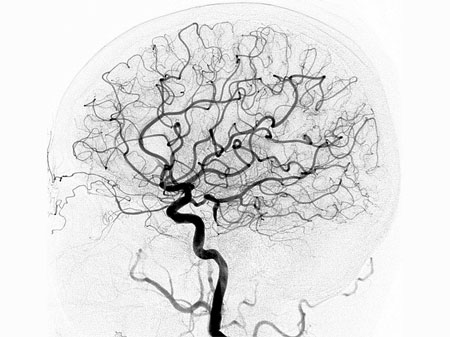

We use the latest diagnostic imaging, such as CT angiogram and catheter-based conventional angiography as well as CT angiography which avoids the risks of catheter techniques, to quickly and accurately diagnose your condition. Our treatments for aneurysms can include open operation (clipping), which involves placing a clamp on the neck of the aneurysm. In addition, we offer non-surgical endovascular treatments

Endovascular Neurosurgery

This is a radiology procedure that looks at how blood is flowing in the brain.

Conditions such as cerebral aneurysms, vascular malformations, vascular tumours, strokes and stroke related symptoms can be diagnosed with a cerebral angiogram

Many patients have no symptoms until the aneurysm ruptures. In some cases, aneurysms can cause headaches or neurologic symptoms before bleeding. Some aneurysms are found prior to breaking or bleeding using CT scanner or MRI. Most people with aneurysms need a cerebral angiography for definitive diagnosis and to determine the best treatment.

The treatment goal with aneurysms is to close off the aneurysm, thereby eliminating the chance of bleeding. This can be done with a surgical procedure to “clip” the aneurysm or an endovascular procedure to “coil” the aneurysm. Clipping an aneurysm is done by opening the skull and placing a clip over the aneurysm.

Endovascular treatment of aneurysmsis a technique which greatly benefits patients with serious medical conditions who are unable to sustain the stress of surgery. Platinum coils are guided into the aneurysm via a catheter, creating a clot that effectively closes the aneurysm off from the surrounding circulation, preventing the risk of haemorrhagic stroke in the future.

Larger aneurysms with wider necks or openings are sometimes treated with other endovascular techniques using a balloon to help keep the coils in position inside the aneurysm, or a small stent, which is a small mesh tube that can keep the coils in place.